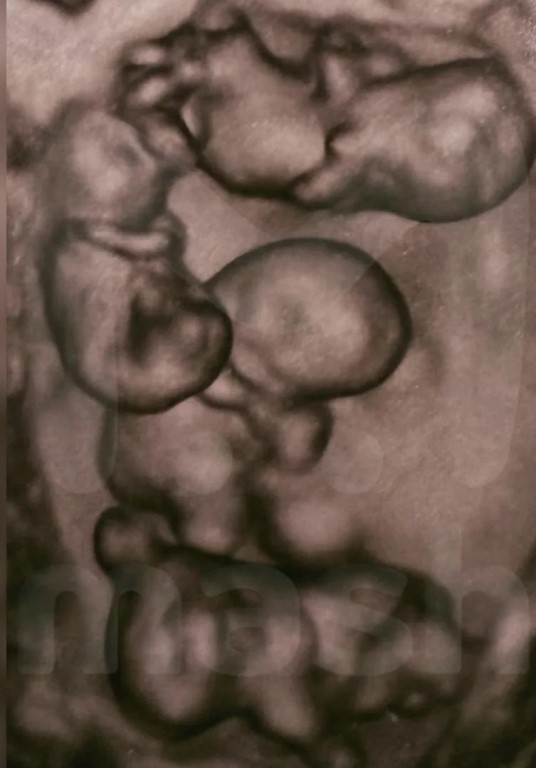

Фото В России впервые родились однояйцевые четверняшки Петербурге впервые в России родились однояйцевые четверняшки, сообщили в роддоме №17. Девочки появились на свет в роддоме №17 на сроке 32 недели беременности, и этот случай считается уникальным – по расчетной статистике такие роды происходят один раз на 15,5 млн. Ранее в стране подобных случаев не фиксировалось. Вес малышек составил от 1,36 до 1,64 килограмма, а рост – от 37 до 41 сантиметра, что специалисты считают отличными показателями для такого срока. Всего в мире 15 таких случаев.